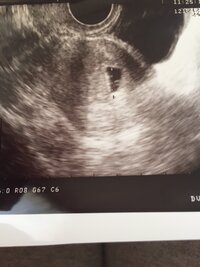

妊娠5週2日 5w2d の超音波 エコー 写真

妊娠5週1日 5w1d の超音波 エコー 写真